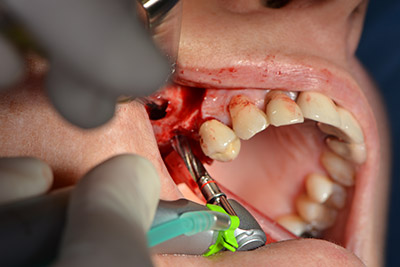

Im nächsten Schritt wird die Sinusbodenelevation mit simultaner Implantation durchgeführt. Für die bukkale Fensterung der Kieferhöhlenwand gibt es auch hier bei der Implantmed an der ersten Position eine Voreinstellung.

Mit 35.000/min wird das Fenster angelegt und anschließend die Schneidersche Membran nach kranial präpariert. (Abb. 13 bis 14).